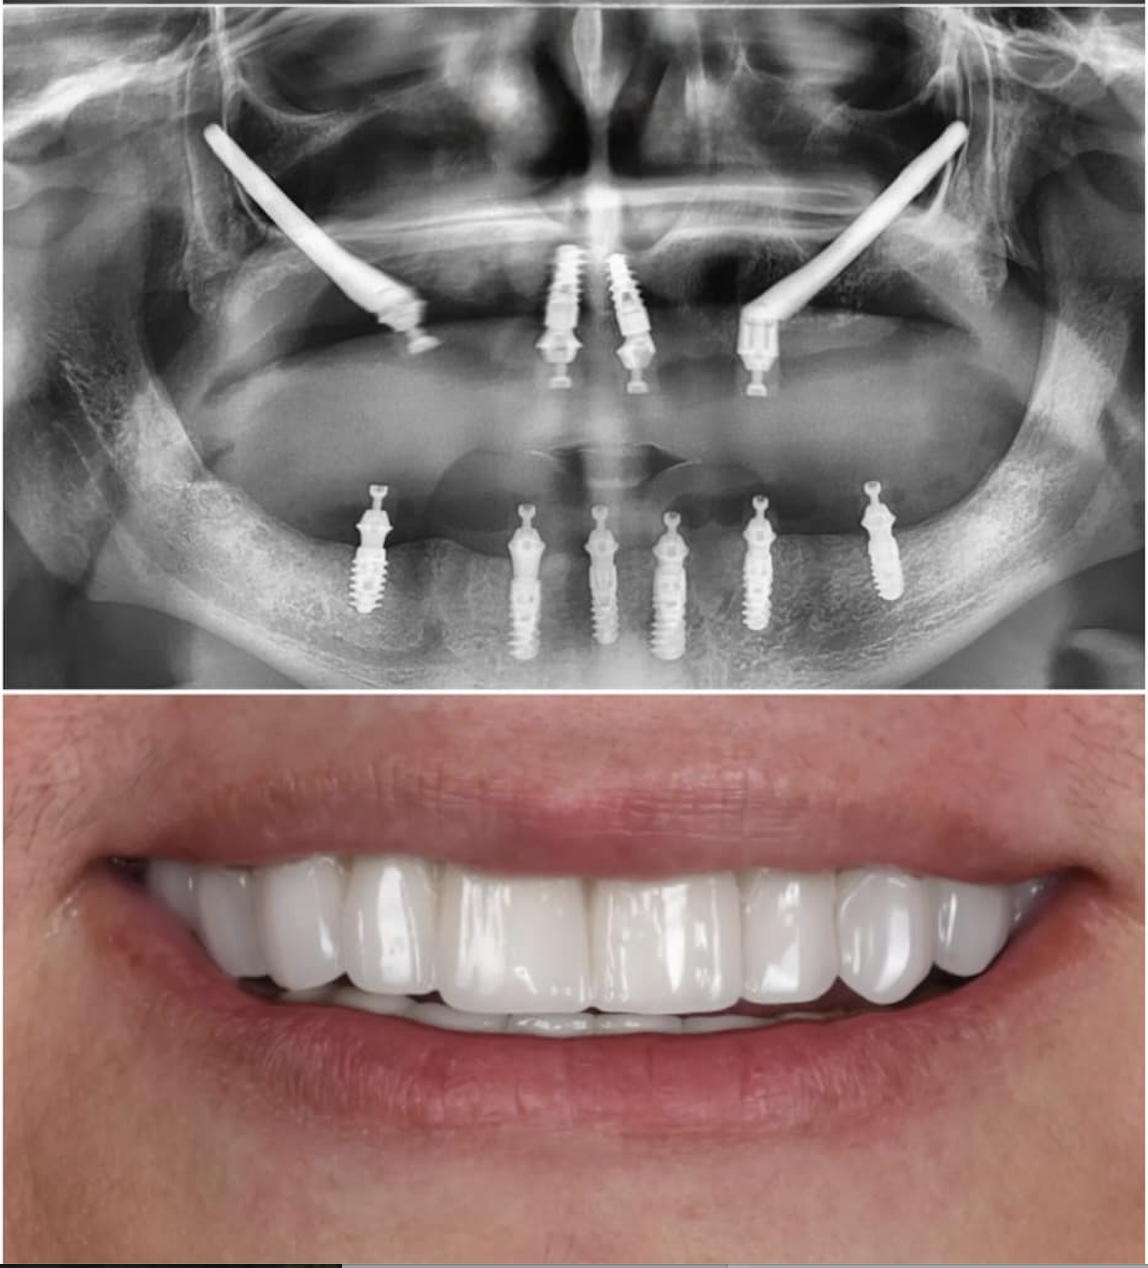

Zygomatic Implants Case Study

Case Study

Advanced Zygomatic

Implant Rehabilitation

Fixed prosthetic rehabilitation with zygomatic implants for a patient presenting with extreme bone deficiency and failed previous implant attempts from another facility.

In this complex case where traditional implant treatments were technically impossible to apply, the ZAGA Concept allowed us to provide a stable, long-term solution through specialized zygomatic surgery, restoring both function and aesthetics.

• Removal of failed implants from external centers

• Severe bone loss management via Zygomatic Concept

• Full functional and aesthetic fixed restoration